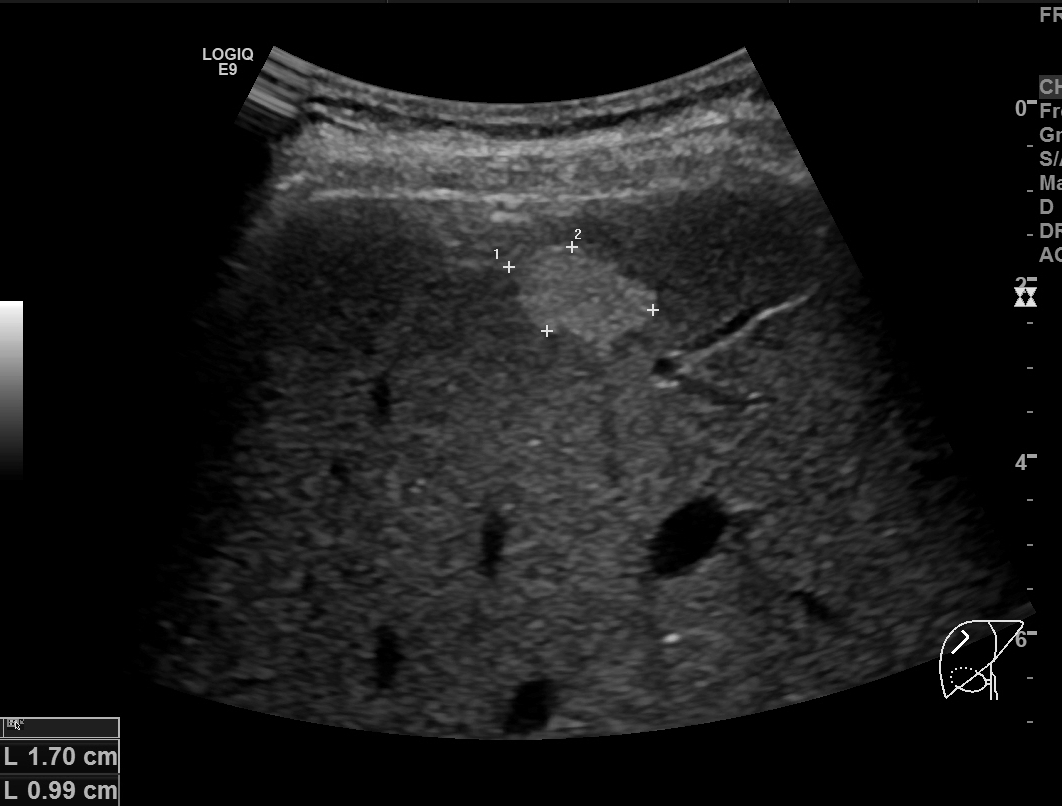

2개월 후 담낭염의 호전여부를 확인하기 위해 간초음파를 시행했습니다. 담낭벽비후는 깨끗하게 호전되었는데, 간우엽에 고에코음영의 종괴가 발견되었습니다. 이전 복부CT영상을 다시 확인해도 전혀 보이지 않는 종괴였으며, 크기가 1.7센티미터로 크기가 작아서 확인이 안될 상황은 전혀 아니었습니다.

종괴는 균일한 고에코음영을 보였지만, 후방에코강조(posterior acoustic enhancement)가 보이지 않았고 모양도 각이 지고 약간 불규칙한 형태를 보였기 때문에 간혈관종의 가능성은 떨어졌기에 추가적인 확인을 위해 간의 다이나믹 조영증강 영상을 추가로 시행했습니다.